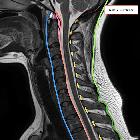

membrane of the spine • Ligaments of the cervical spine (annotated image) - Ganzer Fall bei Radiopaedia

The tectorial membrane is the thin superior continuation of the posterior longitudinal ligament from the body of the axis. It joins the axis body to the clivus on the anterior half of the foramen magnum, and ascends as high as the spheno-occipital synchondrosis and laterally extends to the hypoglossal canal. Anteriorly lies the cruciform ligament. Spinal dura mater is firmly attached posteriorly, also serving as a ligament.